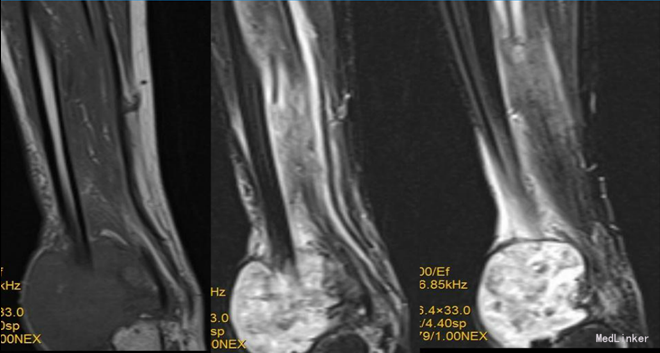

查体:右外踝肿胀,皮肤颜色暗红色,皮温增高,右侧踝可触及质韧肿物,基地广泛,移动度差,肿物按压有轻度胀痛,无叩痛。 辅查:右胫腓骨X线片示:右胫腓骨远端骨质缺失,周围软组织肿胀,不除外骨肿瘤,建议进一步检查。行MRI示:右胫腓骨远端肿物,考虑恶性肿瘤。实验室检查未见明显异常。

入院诊断:右胫腓骨肿物。入院后行穿刺活检,活检病理示:送检组织见成簇大小不等增生的血管,血管间可见增生的纤维母细胞及硬化的胶原,部分似毛细血管,血管内皮细胞增生,少许呈乳头状伴有纤维素渗出,成簇增生的小血管想骨组织内浸润性生长;结合影像学改变考虑侵袭性血管瘤病。患者予唑来膦酸治疗,治疗后骨化明显,右踝关节胀痛明显缓解。